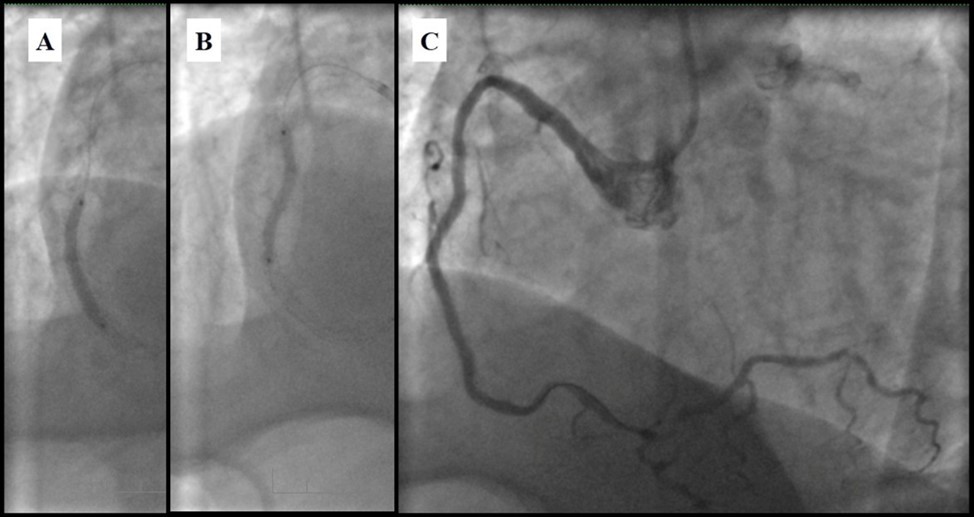

Due to financial problems the second stage was performed after 3 months (during this time the patient solved his financial problems). CAG revealed patent stents in LAD (Figure 7), and 60-70% restenosis by BMS in RCA (Figure 8). In-stent restenosis was treated by plain old balloon angioplasty (POBA), the optimal result was obtained (Figure 9). After LMCA quadrifurcation balloon predilation, 2.5×26 mm DES (Resolute Integrity, Medtronic) was implanted in the IMA, using a modified balloon mini-crush technique. The stent was minimally protruded in the LMCA and its edge was crushed by preloaded MB balloon. Next 2.5×30 mm DES (Resolute Integrity, Medtronic) was implanted in OM1 through the CX (first marginal and circumflex arteries in this particular case have the same ostium). The stent was protruded in the LMCA as in conventional modified balloon crush stenting technique, after stent deployment, its balloon was pulled back and overinflated, then protruded stent was crushed by preloaded MB balloon (Figure 10). 3.5×15 mm DES was implanted in the LMCA so that distal part of the stent covered ostial and proximal segments of the LAD. Sequential post-dilatations were performed using a kissing balloon technique (1. LMCA-LAD-IMA,2. LMCA-LAD-CX-1OM). After post-dilatations, through the stent implanted in CX-OM1, coronary wire and smaller diameter balloon (2.0 mm) were advanced in direction of the CX mid-segment and by balloon dilatation stent’s strut was opened (provisional stenting technique for CX). Finally, the proximal optimization technique was performed in the LMCA using a 3.5 mm diameter non-compliant balloon (Figure 11). The final angiographic image was good, the intervention ended without complications (Figure 11, Figure 12). We could not confirm the result with IVUS or OCT due to several technical and financial problems (not covered by insurance). 1 month after PCI, at regular checkout, the ejection fraction was 48%, the functional class of the Congestive Heart Failure decreased from class II-III to class I and the patient complaints have been disappeared.

Figure 9.RCA; A, B - Plain old balloon angioplasty; C - Angiography result.